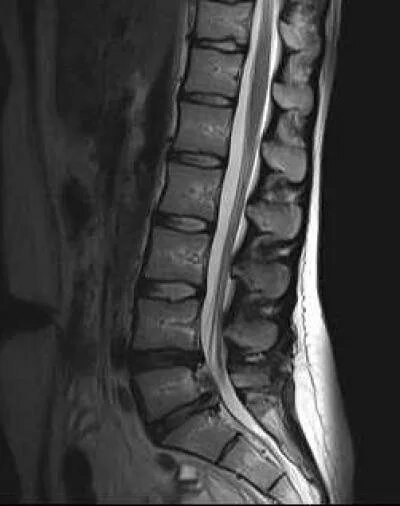

Протрузия в дуральном